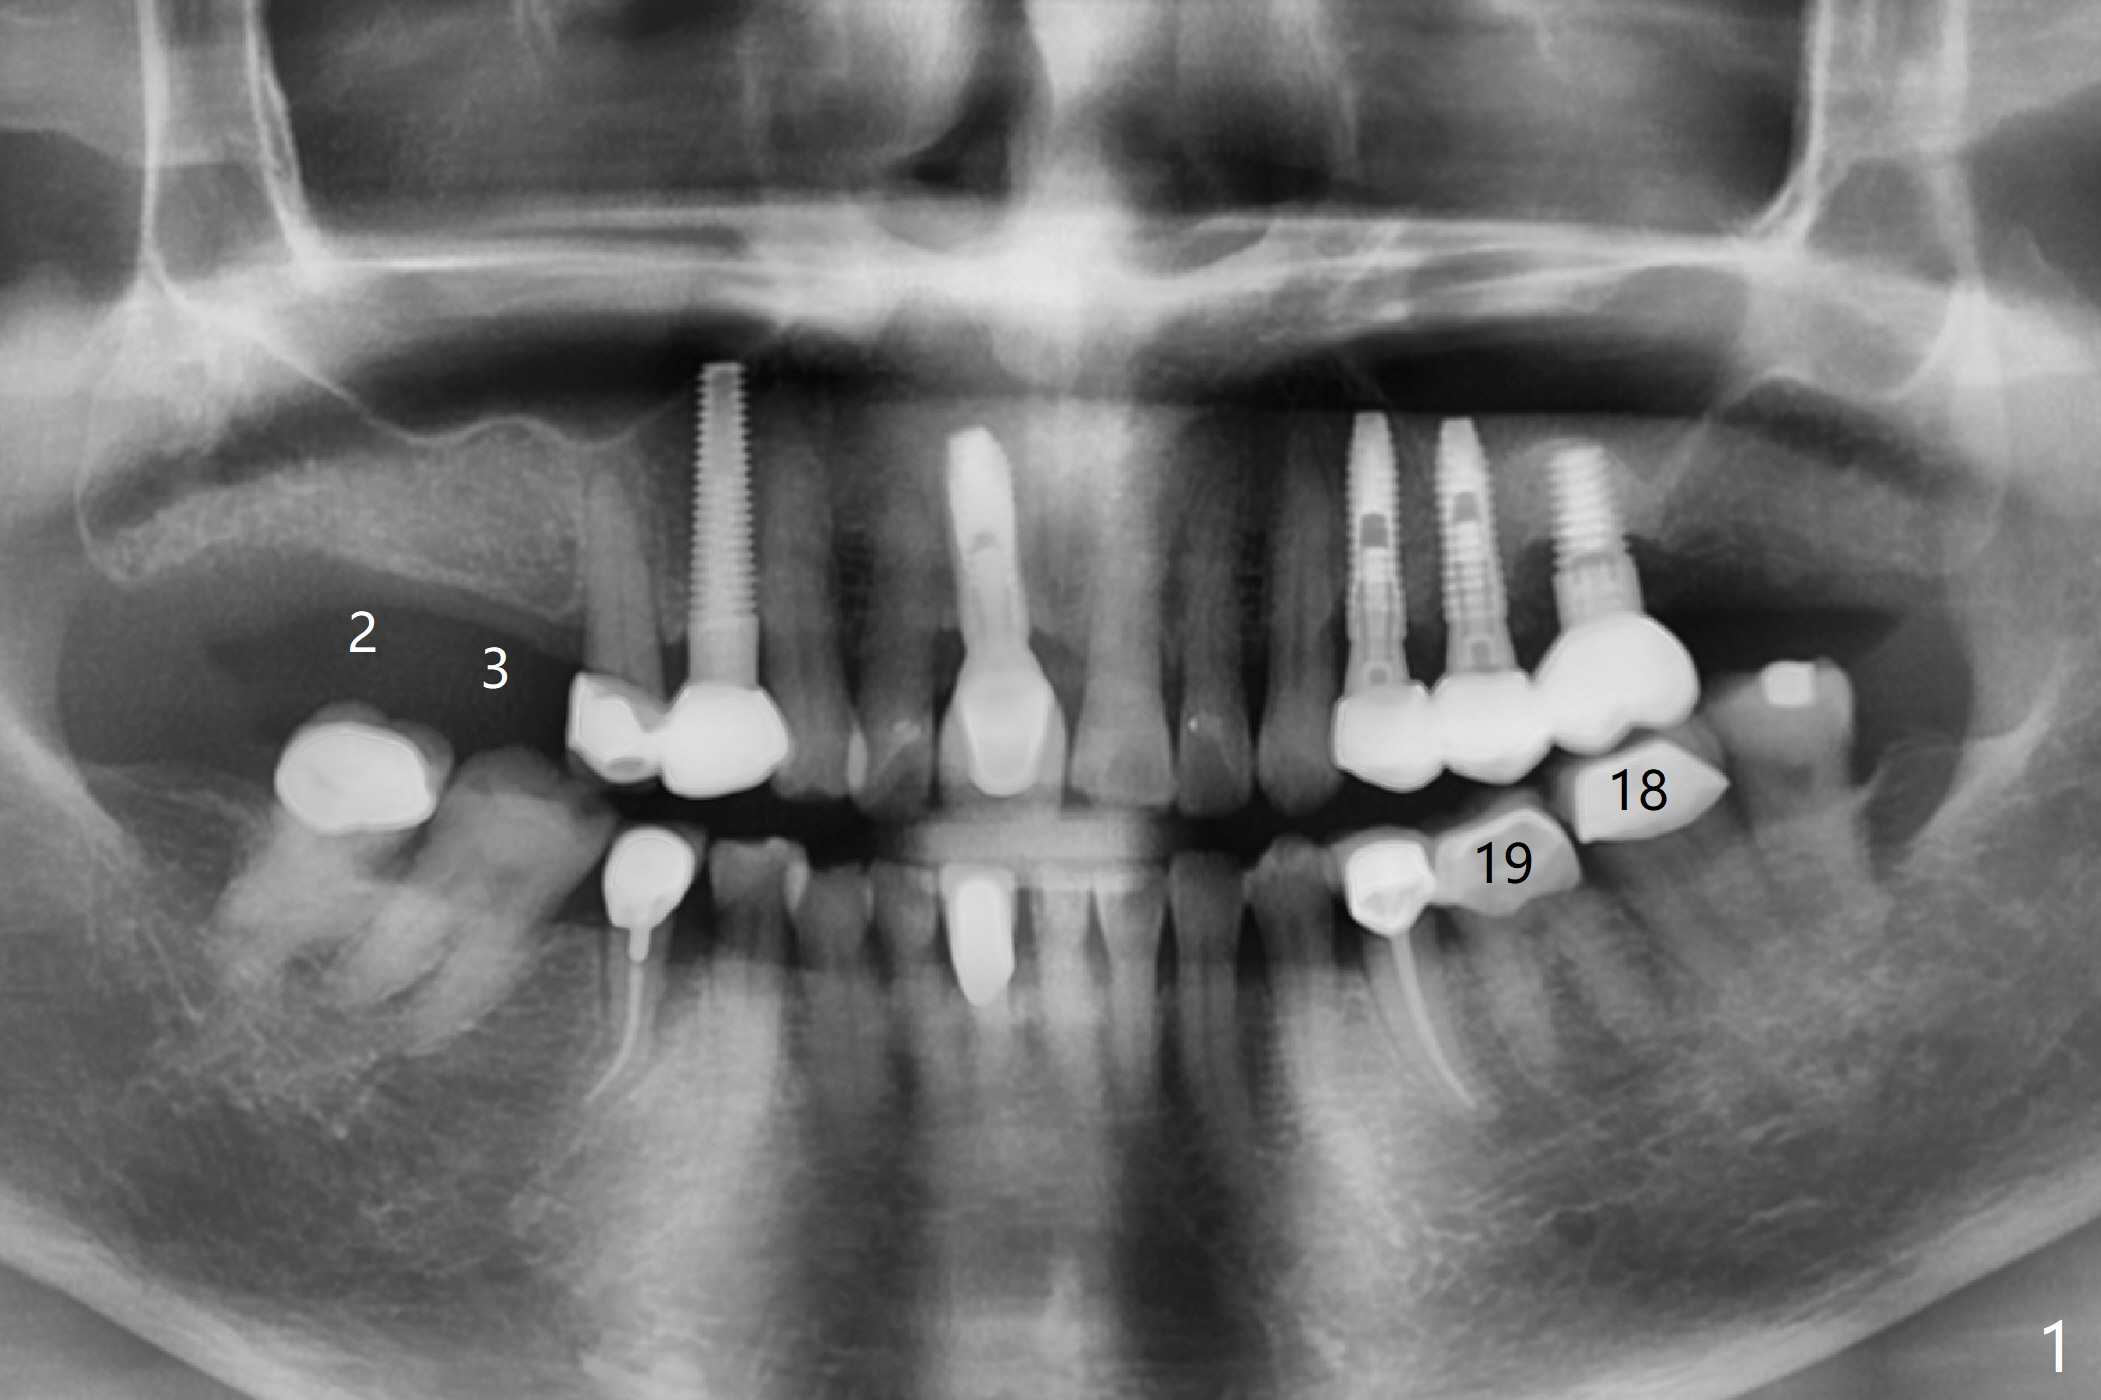

A 74-year-old woman needs cementation at #18 and 19 because of missing teeth at #2 and 3 (Fig.1). It will be efficient to place 2 implants with guided surgery. A challenge is limited bone height (Fig.2); sinus lift is required. After finishing osteotomy, remove the guide for sinus lift using Sinus Lift Master kit. Return the guide and finish implant placement.